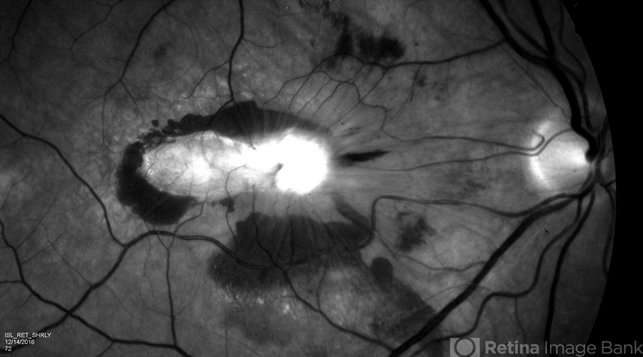

- black and white photo, subretinal hemorrhage, subretinal thickening, red-free, fibrosis, fibrotic scar

- Red free image, fundus photograph, of a 52-year-old white male with VA loss to 20/200 of unknown etiology. Dilated fundus examination of the right eye reveals a fibrotic scar with subretinal thickening and subretinal hemorrhage.